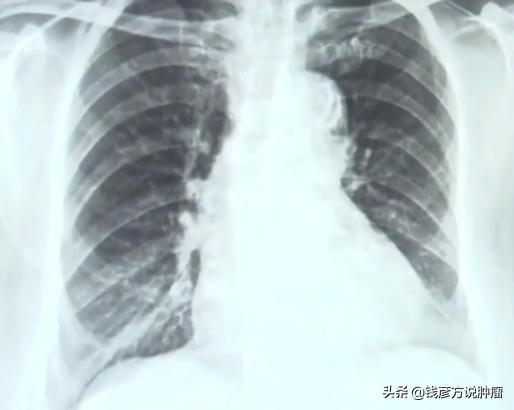

这位女士是一位肺癌晚期患者,患者2009年体检发现肺上有索状条纹,体检医生让她去综合医院去检查,结果是双肺多发性的磨玻璃结节,去过北京的很多家医院都说是磨玻璃结节。

肺部结节是一种影像学的描述,是指肺部可见局灶性,类圆形密度增高的阴影。

她是从肺上发现的一个3厘米大的阴影,我们就叫结节,这个结节实际上分为几种结节,一个是实性结节、一个是磨玻璃结节,还有一个是混合性结节。

如果是磨玻璃结节它的发病率是很高的,有统计大概有60%-70%有可能是恶性的,另一个如果出现混合性结节,就是在磨玻璃结节的情况下有部分致密阴影,恶性程度在80%以上。

到了2011年12月份患者的病灶原位又有了阴影,没想到的是等到过完年做检查肿瘤已经长到5厘米了。